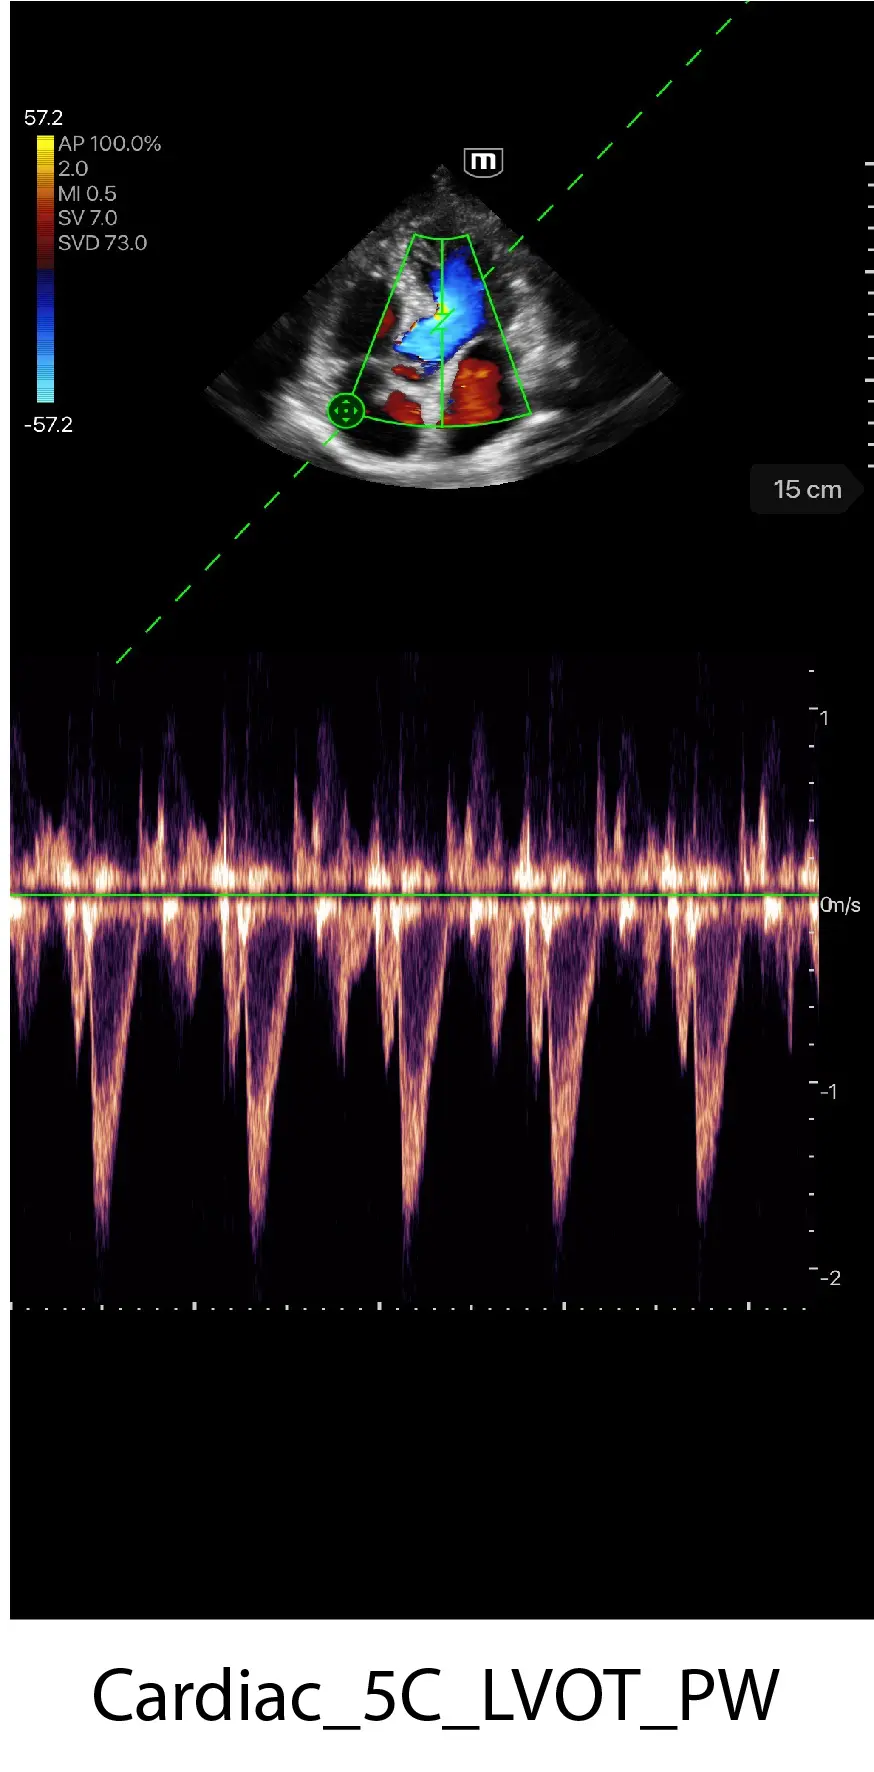

Клинични снимки